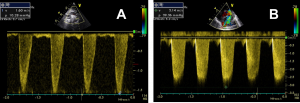

Con el Doppler pulsado (PW) se registra la velocidad en un punto concreto mientras (Figura A) que en el continuo (CW) se registra la velocidad máxima o el gradiente máximo en la zona donde se coloca el cursor (a lo largo de toda la línea) (Figura B) y éste se usa para cuantificar velocidades altas (estenosis).

La velocidad del flujo sanguíneo se utiliza para el cálculo de gradientes transvalvulares y la determinación de presiones intracardíacas, y para diferenciar un flujo laminar del flujo turbulento patológico en el que las células sanguíneas van a diferente velocidad y se representan por una banda ancha.

El cálculo de los gradientes es una estimación de la gravedad de ésta, se utiliza la fórmula de Bernoulli: Gradiente (mmHg) = 4 x V2, donde V es la velocidad máxima del Doppler en metros/segundo